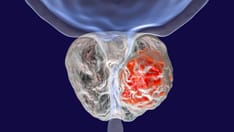

How Selenium, Vitamin E Increase Prostate Cancer Risk

New data from the much publicized Selenium and Vitamin E Cancer Prevention Trial (SELECT), which sought to determine whether these supplements could protect against the development of prostate cancer, confirm that both antioxidants can be risky business for men.

As previously reported, men receive no preventive benefit from either selenium or vitamin E supplements; in fact, for certain men, these supplements actually increased the risk for prostate cancer.